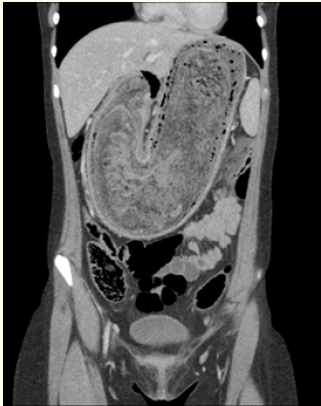

Successful Laparoscopic Management of Giant Hydatid Liver Cyst: A Case Report

Loai Saleh Albinsaad, Arshadullah Khan, Mohammed Yousef Alessa, Ali Abdulhamid Almohammed saleh and Abdulmohsen Yaseer Alkhars. 6(3): 19-24.